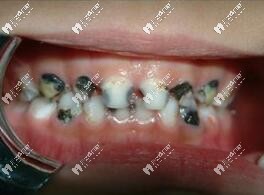

兒童應(yīng)該3歲開(kāi)始看牙,在這期間如果不重視,孩子有齲齒不及時(shí)發(fā)現(xiàn),會(huì)導(dǎo)致孩子牙痛難忍,換牙期(6 歲一12歲)更要定期到醫(yī)院檢查牙齒,因?yàn)榭赡軙?huì)出現(xiàn)換牙時(shí)間、順序不對(duì),牙齒長(zhǎng)得不整齊, 所以定期請(qǐng)兒童口腔醫(yī)生檢查是必要的。

兒童齲齒圖片

兒童齲齒也要及時(shí)補(bǔ)牙,蛀牙到牙神經(jīng)也會(huì)引起疼痛,而且不及時(shí)補(bǔ)牙,牙齒齲壞到根尖有可能隱形恒牙發(fā)育,可謂小洞不補(bǔ)大洞吃虧。